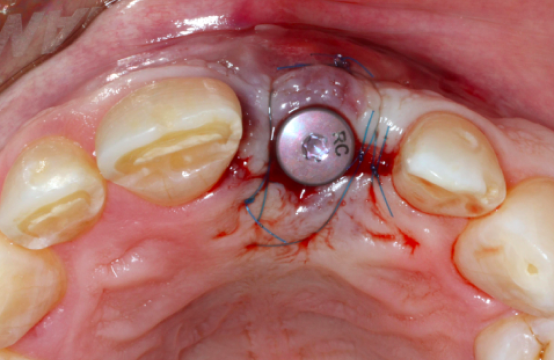

Surgical Site Preparation Process

Socket Preservation for implant

3 Months

3 Months

Implant 21

Surgical Site Preparation Process

Socket Preservation for implant

Socket Graft of 21: 3 Months

Implant 21